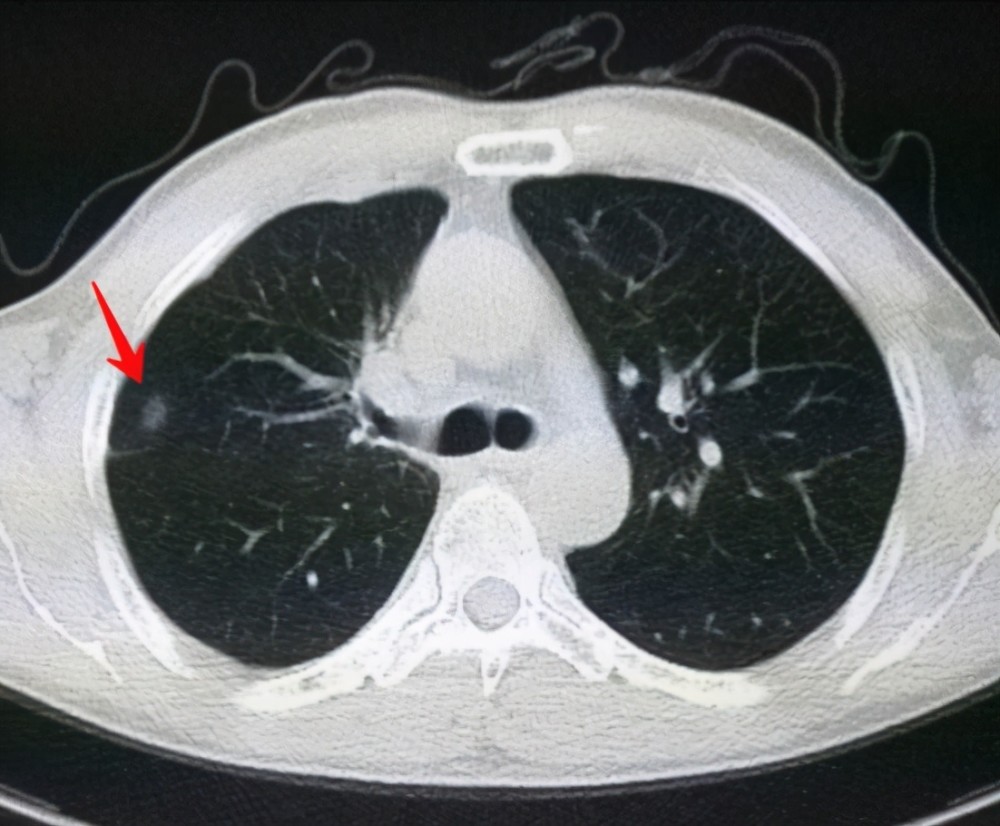

肺結(jié)節(jié)是一種常見的肺部疾病,其發(fā)病率逐年上升,雖然肺結(jié)節(jié)多數(shù)情況下是良性的,但也有可能惡化為肺癌,了解肺結(jié)節(jié)的形成原因?qū)τ陬A(yù)防和治療具有重要意義,本文將為您詳細解析肺結(jié)節(jié)的形成機制。

肺結(jié)節(jié)的形成原因

1、環(huán)境因素

環(huán)境因素是肺結(jié)節(jié)形成的重要原因之一,長期暴露于污染環(huán)境中,如空氣污染、化學(xué)污染等,可能導(dǎo)致肺部吸入有害物質(zhì),從而引發(fā)肺結(jié)節(jié),長期接觸石棉、硅塵等職業(yè)環(huán)境因素也可能增加肺結(jié)節(jié)的發(fā)病風(fēng)險。